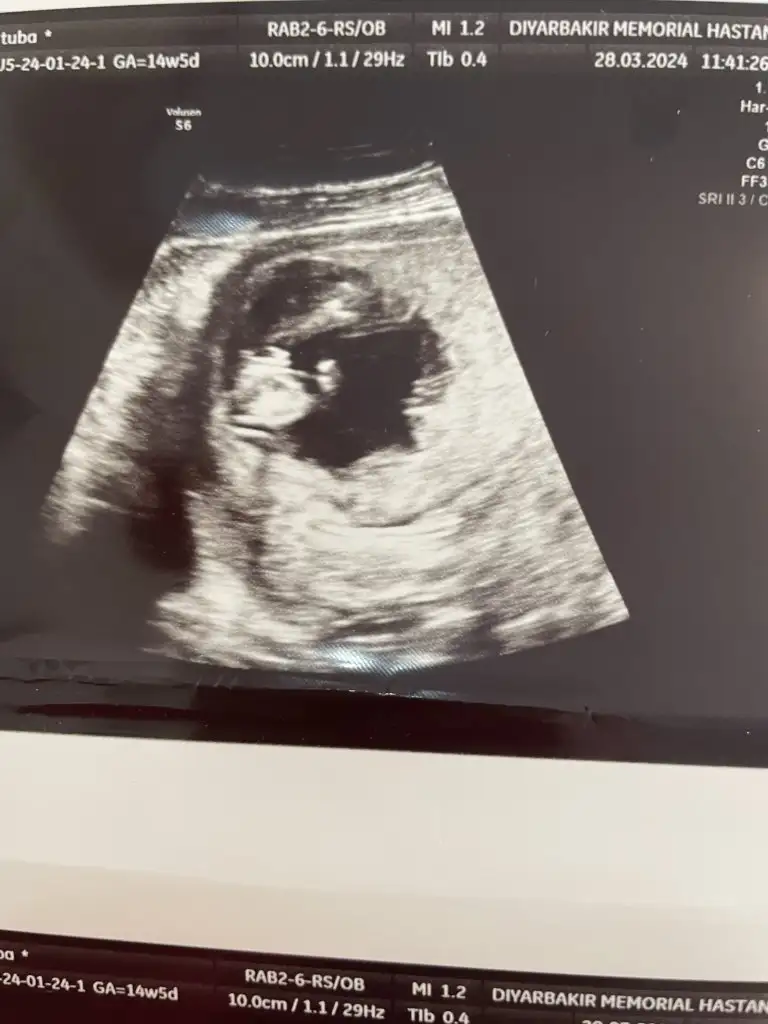

Oyyh ojbuldum canımtatlım hayırlı uğurlu olsun inş, erkek anaları olarak aramıza hoşgeldiniz diyelim :)) inşallah sorunsuz ilerlemeye devam ederiz ve sağlıkla bebeklerimizi kucağımıza alırız

Analarının kuzuları hepiciği

Bu sabah günaydın oğluşum diye selamlaştık, şimdiden keyfi bile alıyor aklımı